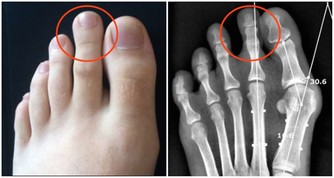

消化道出血或惡性腫瘤:消化道出血時,血液在患者的腸道中聚集。胃酸及腸道細菌將血液分解後,排出的屁有腥臭味。患腸道惡性腫瘤時,癌組織糜爛、出血,再加上細菌的分解發酵作用,也會使放出的屁有腥臭味。

若屁奇臭難聞,可能有消化道出血、菌痢、阿米巴痢疾、潰瘍性結腸炎、出血性小腸炎等炎症。此外,惡性腫瘤晚期,因癌腫組織糜爛,蛋白質腐敗,由於細菌的作用,放出的屁也會很臭。愛放屁且經常放臭屁的人就有可能患上大腸疾病,這時你就需要前去診斷了。

如果消化道出血時, 血液在腸腔內滯積, 或腸道發生炎症、潰瘍時, 排出的氣體往往比較腥臭,最好找醫生進行診治,這可能是罹患胃腸道腫瘤的警訊。當患有腸道惡性腫瘤時, 由於癌腫組織糜爛,, 蛋白質腐敗, 經肛門排出的氣體也可出現腐肉樣奇臭。